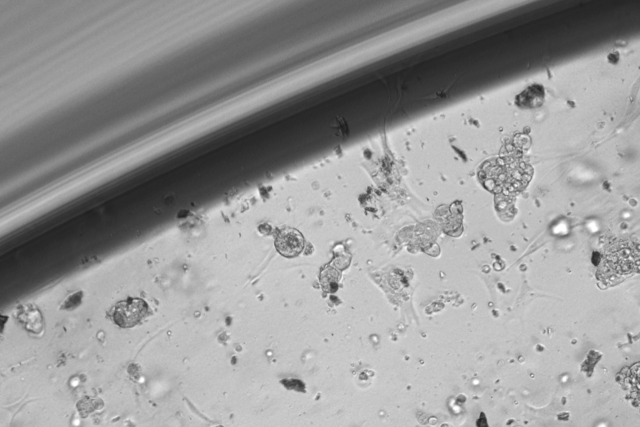

The image shows chordoma organoids growing.

The screening method uses patients' own cells, collected during surgery, to create miniature tumor organoids. Organoids are simpler, smaller versions of bodily organs or tumors that scientists can grow in a lab to replicate the full-function structures; researchers create them to study diseases and possible treatments.